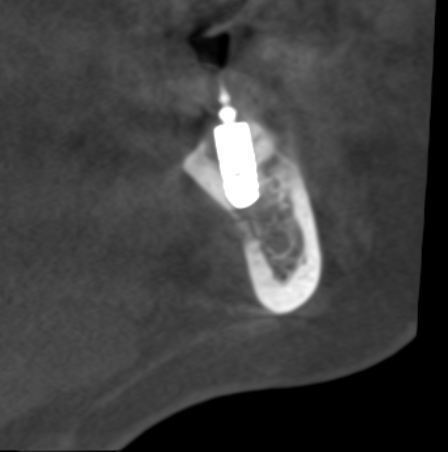

Но, насколько долговечен подобный результат остеопластики? Посмотрим на КЛКТ через 18 месяцев:

или

Как видите, даже структурно регенерат не отличается от подлежащего альвеолярного гребня, хотя заметен на снимке своей неестественной формой. Это говорит о том, что результат остеопластической операции стабилен, и мы можем быть спокойны за дальнейшую судьбу имплантов.